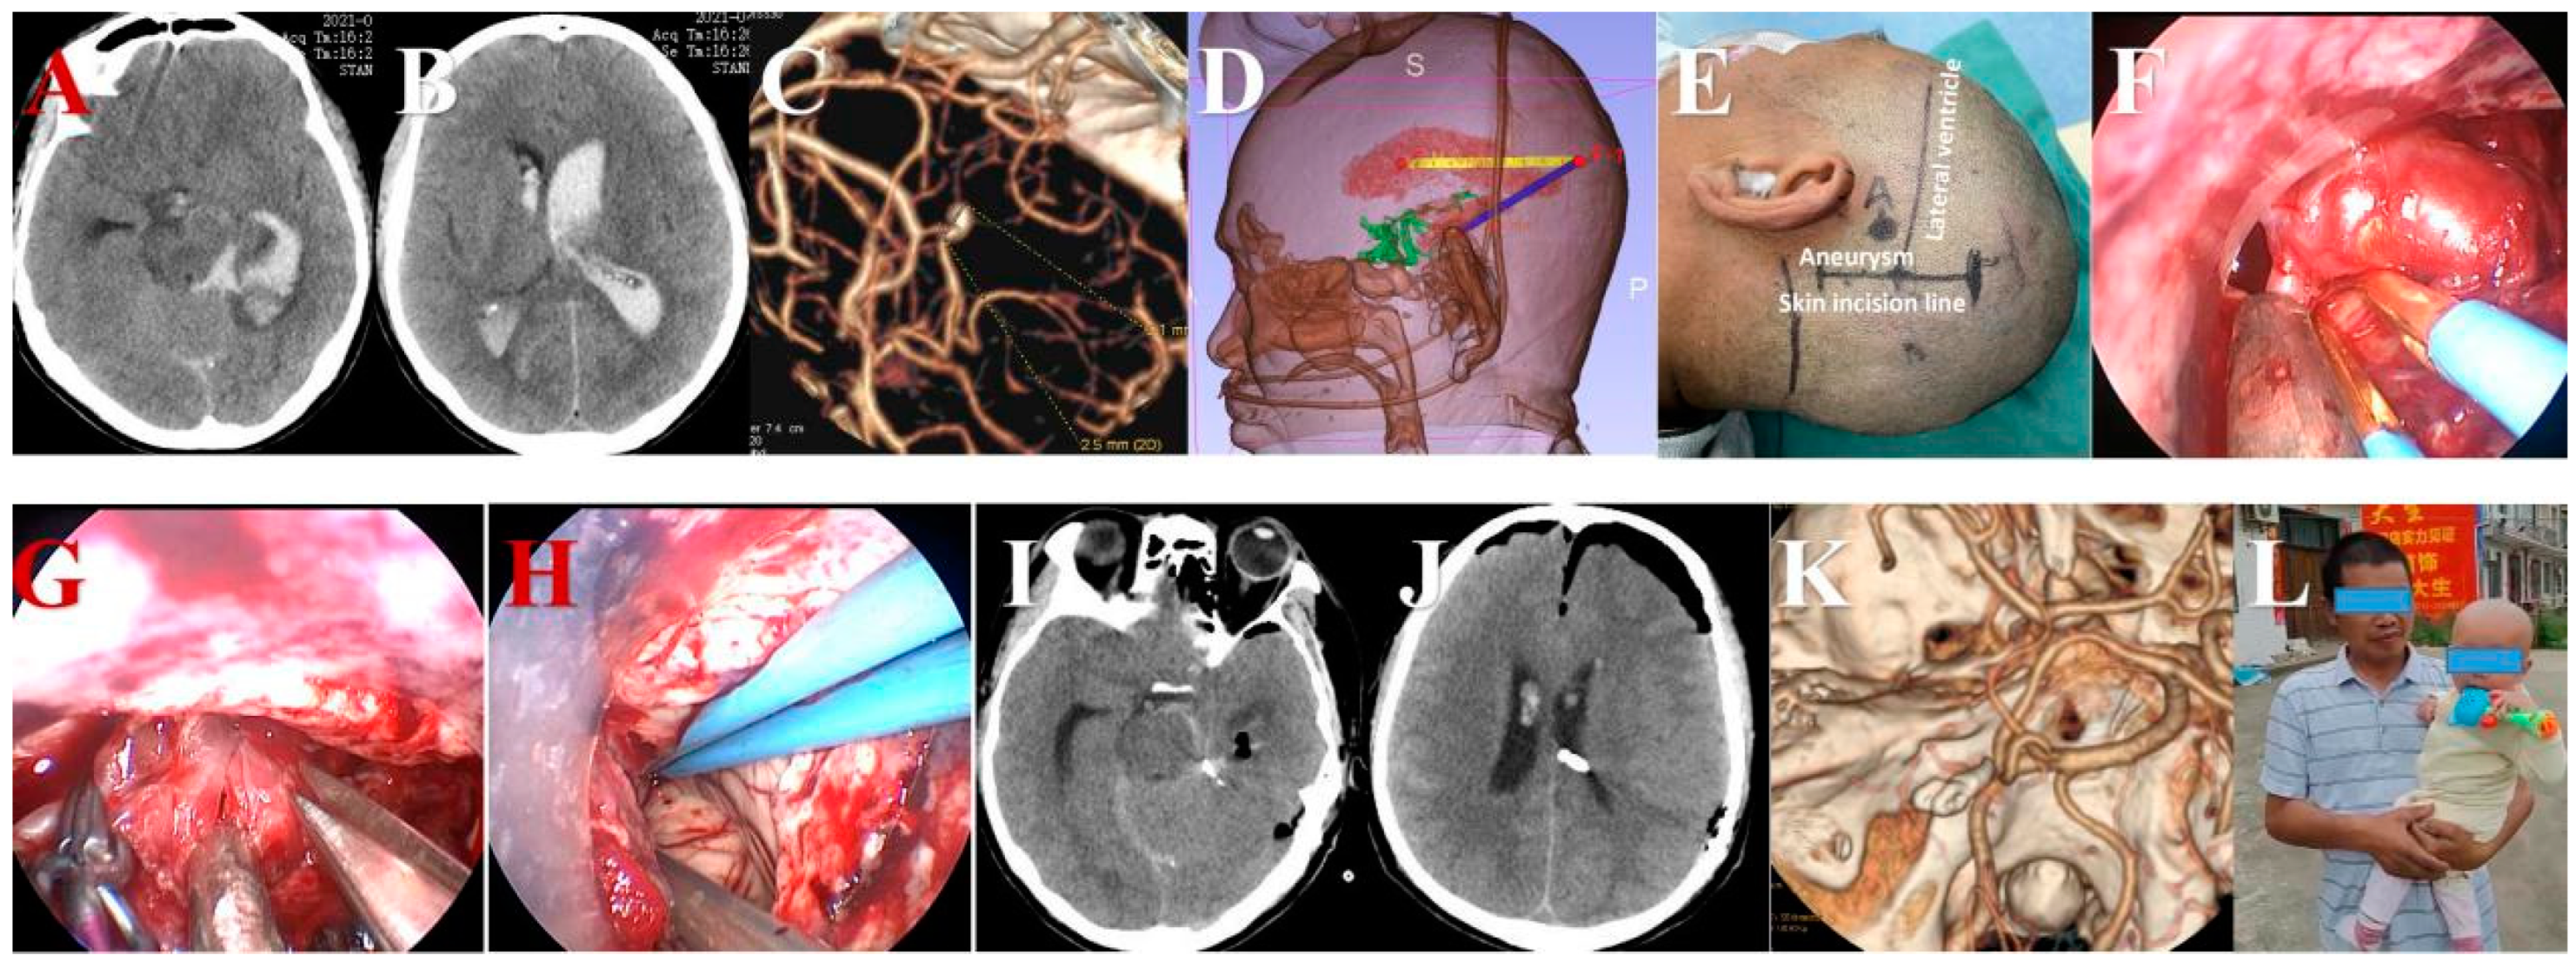

Surgical Clipping of Intracranial Aneurysms Using a Transcranial Neuroendoscopic Approach

2.3. Surgical Procedures